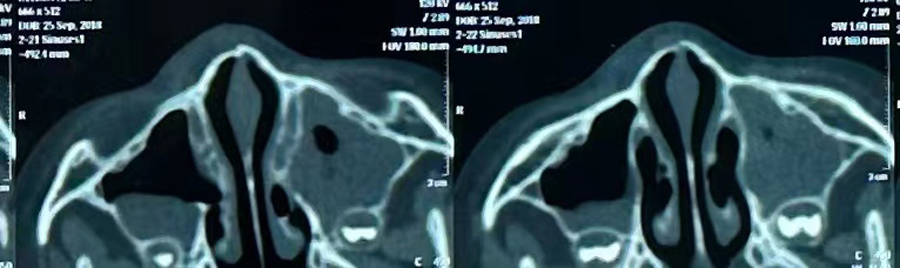

8月15日,彬彬家长在辗转多家医院后,听说a片网站 有鼻骨骨折复位新技术,立即带彬彬赶到医院。此时,距离彬彬鼻骨骨折已经过去一周了。就诊时,彬彬鼻部肿胀已经消退了,能看到他的鼻梁是向左侧偏曲的,妈妈特别希望孩子的鼻梁能恢复到从前高挺、居中的状态。国家儿童医学中心、北京儿童医院耳鼻喉头颈外科常驻专家、a片网站 副院长张薇,a片网站 耳鼻喉科主任李莉萍为其进行鼻部检查,并结合鼻骨CT全面评估后,决定采用超声引导下鼻骨骨折复位术,以实现精准复位,使彬彬的面容不受影响。8月16日,张薇副院长、李莉萍主任及手术室、麻醉科医护人员组成手术团队,为彬彬进行手术。术中,医生在超声引导下应用复位器对游离骨片进行复位调节,使错位的鼻骨重新连续。10分钟后,手术顺利完成,复位后的鼻子外观无畸形。术后,彬彬接受抗感染治疗48小时,情况稳定,顺利出院。

相比较传统凭经验及手感的鼻骨复位术,超声引导下的手术复位能更精准定位到损伤部位,如医生的“透视眼”,实现手术可视化,使医生在术中可准确看到鼻骨断端的对合情况,在“精准、微创、美观”上得到极大优化和提升。患儿无伤口、恢复快。术前和术后鼻骨错位及对合情况B超均有图片准确显示,让家长也能看明白,患儿和家长的心理负担明显减轻不少,改善了就医体验。